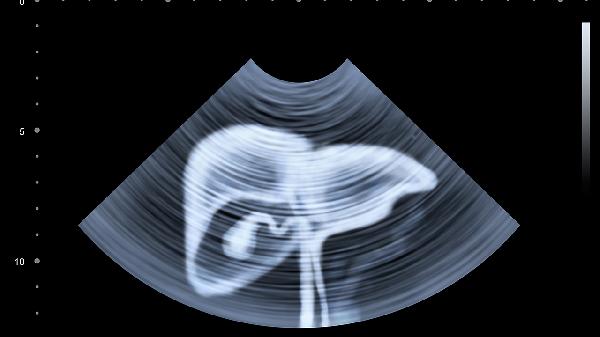

左侧输尿管结石可引发突发性刀割样疼痛,向会阴部放射,伴血尿、尿频。肾结石移动时疼痛尤为剧烈,可能引发肾绞痛。超声或CT可明确结石位置,较小结石可通过多饮水、服用排石颗粒促进排出,较大结石需体外冲击波碎石。

女性左侧附件炎、卵巢囊肿蒂扭转或异位妊娠可引起左下腹坠痛,疼痛性质与月经周期相关。附件炎常伴阴道分泌物增多,异位妊娠可能出现停经后阴道出血。需妇科检查联合超声诊断,急腹症情况需紧急手术干预。